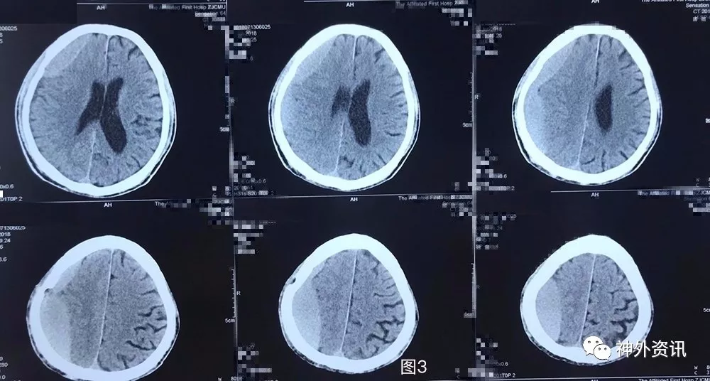

图3. 外院第2次手术前头颅CT:右侧额颞顶枕硬膜下血肿复发,血肿为稍高密度,脑实质受压,中线轻度左偏。

图4. 第2次手术后1天头颅CT提示:右侧额颞顶枕硬膜下血肿钻孔引流术后再次局部血肿形成。

图5. 第2次手术后4天头颅CT提示:右侧额颞顶枕硬膜下血肿局部血肿继续增大。